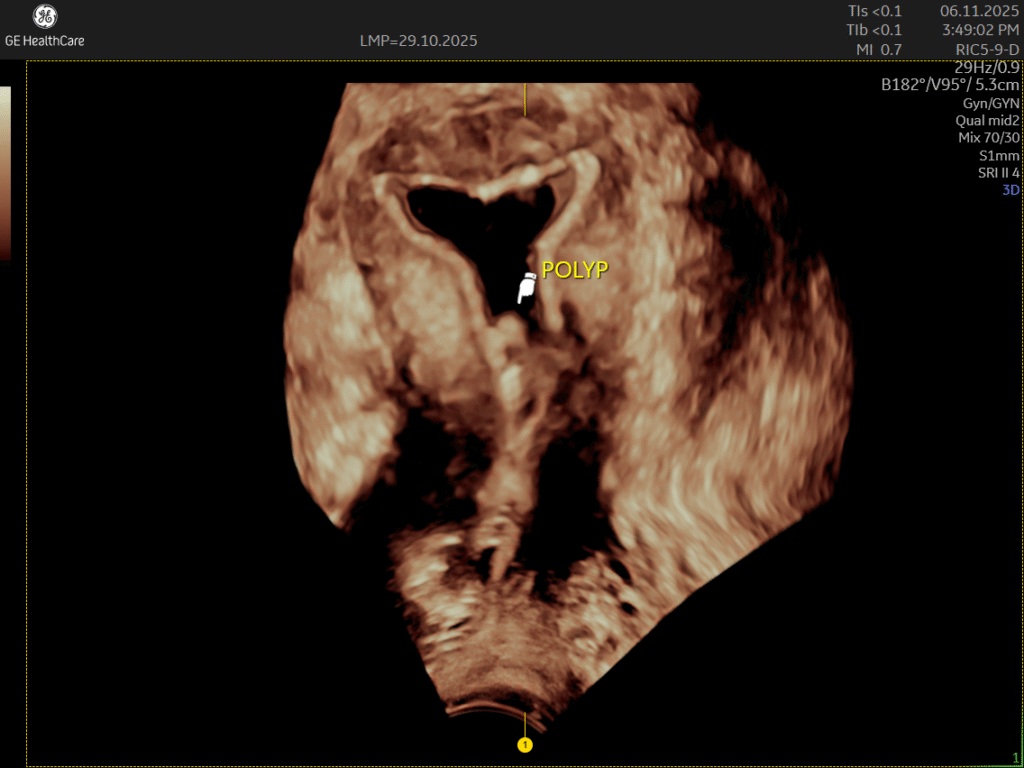

Saline Infusion Sonography (Day 5 – Day 12)

Saline Infusion Sonography (SIS) | Uterine Cavity Assessment at NESA What Is Saline Infusion Sonography? Saline Infusion Sonography (SIS), also